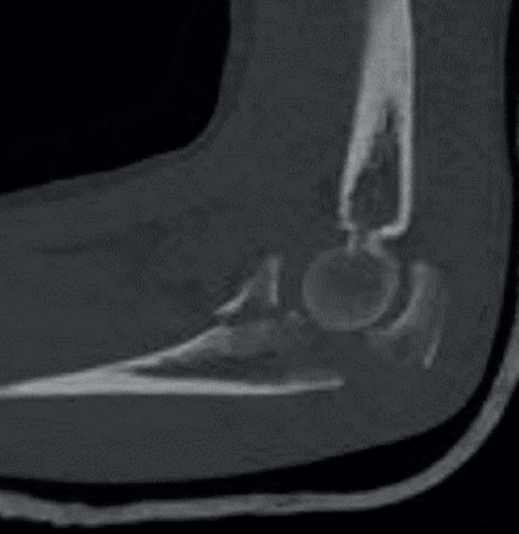

Se han definido 3 patrones de lesión (Tabla 2). Las fracturas de tipo I de O’Driscoll son fracturas que afectan a la punta de la coronoides, están generalmente asociadas con la llamada tríada terrible (fractura de coronoides, fractura de la cabeza del radio y luxación posterior o posterolateral de codo)(5). Suelen acompañarse de rotura del LCL. Las fracturas de tipo II son las que afectan a la faceta AM. Están asociadas con el cuadro de inestabilidad rotatoria posteromedial en varo (VPMRI) y suceden generalmente tras un cuadro de subluxación (no luxación completa)(6). Las lesiones asociadas incluyen la avulsión del LCL del epicóndilo. La cabeza del radio no suele estar afectada. Las fracturas de tipo III son fracturas grandes que afectan al 50% o más de la altura de la coronoides y se asocian con fractura-luxación del olécranon. Las luxaciones por fractura del olécranon anterior presentan una luxación anterior del antebrazo con una articulación radiocubital proximal (RCP) intacta. La fractura de coronoides, en este patrón de tipo III, suele ser un único fragmento grande y los ligamentos suelen permanecer intactos (Figura 3). Se cree que las luxaciones por fractura del olécranon anterior son causadas por un golpe directo en la cara posterior del codo flexionado y con el impacto el húmero pasa a través de la escotadura troclear del cúbito. Las luxaciones por fractura del olécranon posterior se caracterizan por una conminución del olécranon y la apófisis coronoides, un desplazamiento posterior del radio con respecto al capitellum y una fractura de la cabeza del radio. El LCM suele estar intacto en la coronoides fracturada y el LCL sufre una avulsión proximal. Como vemos, en la gran mayoría de los casos tendremos que reparar el LCL, que puede estar afectado en cualquiera de los 3 patrones, además de tratar la fractura de coronoides, así como el resto de las lesiones si lo precisan. Algunos autores defienden que, en fracturas de tipo I y alguna de tipo II con articulación congruente, la reinserción del LCL sin fijación de la fractura de coronoides puede ser suficiente para mantener la estabilidad del codo(7).